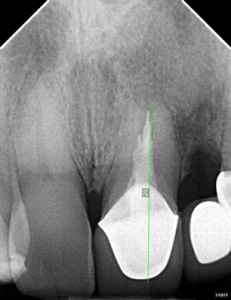

Root Canal / Retreatment

Clinical Cases